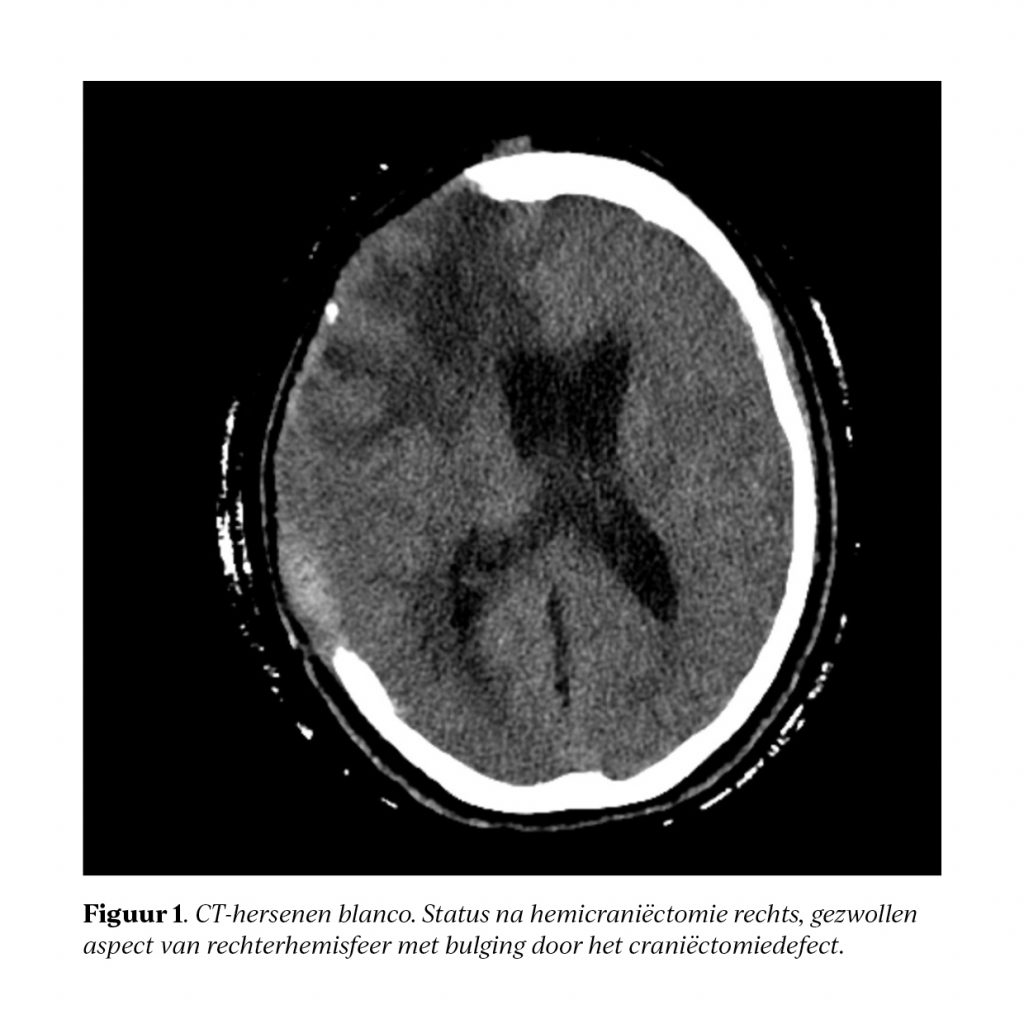

De revalidatiegeneeskunde werd betrokken om een passende revalidatiebehandeling binnen het ziekenhuis op te zetten en ook een passend vervolgtraject te bepalen. Bij eerste beoordeling zagen wij een vrouw met een schedeldefect die te wekken was op aanspreken, met een hypertone hemiparalyse aan de linkerzijde, gestoorde zitbalans en nauwelijks spontane spraak. Zij voerde eenvoudige opdrachten uit en communiceerde voornamelijk met gebaren. Multidisciplinaire revalidatie werd opgestart en ondanks haar initieel beperkte belastbaarheid werd gekozen voor klinische revalidatie binnen de medisch-specialistische revalidatie (IMSR). Gedurende klinische revalidatie verliep het herstel moeizaam, en na ongeveer een maand trad zelfs duidelijke achteruitgang op in haar functioneren: gedragsverandering, cognitieve achteruitgang, visuele hallucinaties en wanen, weigeren van medicatie/voeding, en zichtbaar ingevallen huid bij de botlap. Er werd overlegd met de neurochirurg met verzoek patiënte aan te melden voor cranioplastiek vanwege een vermoeden op het post-trepanatiesyndroom. Differentiaal diagnostisch werd een delirant beeld overwogen bij verminderde voedingsstatus, verstoord slaapritme, dan wel onderliggend lijden. Patiënte werd ingestuurd naar de SEH, alwaar ander onderliggend somatisch lijden werd uitgesloten. Hiermee werd het post-trepanatiesyndroom waarschijnlijker geacht.

Naast klinische achteruitgang kunnen een ingevallen botlap (sunken skin flap) en radiologische verschijnselen (bijvoorbeeld een paradoxale midline shift of paradoxale herniatie) de diagnose ondersteunen. De ingevallen botlap is echter niet altijd aanwezig, en deze radiologische verschijnselen kunnen ook bij andere aandoeningen voorkomen.2 Het brede en aspecifieke klachtenpatroon maakt het syndroom lastig te herkennen, waardoor het waarschijnlijk ondergerapporteerd is.3